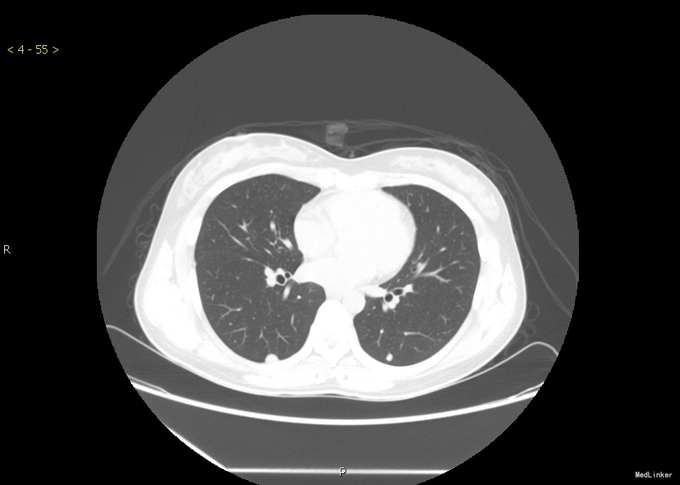

主 诉:发现肺部占位半个月 现病史:年轻女性,患者半月前体检时发现右下肺肿块,胃纳可,无诉特殊不适,大小便正常,体重无减轻。

查体:无特殊。 辅查: CT提示:双肺下叶及右肺中叶多发结节灶,考虑为肺转移瘤, 肺穿刺活检:(右肺)低分化腺癌,转移性,考虑涎腺肿瘤转移。